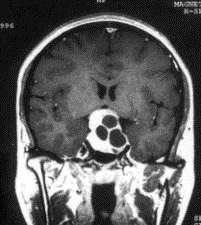

问题 病历摘要:??患者男性,35岁。性功能减退2年,视力下降6月。既往体健。体检:神清,皮肤细腻,毛发稀疏。视力左眼0.3,右眼0.5,双瞳等大等圆,直径3.5mm,对光反射稍迟钝,双颞侧偏盲,双眼底视神经乳头原发性萎缩,余神经系统未见异常。 入院后应申请哪些辅助检查?

选项 A.内分泌功能检查 B.脑电图 C.头颅平片 D.头颅MR E.TCD F.SPECT G.CT H.PET

答案 ACDG